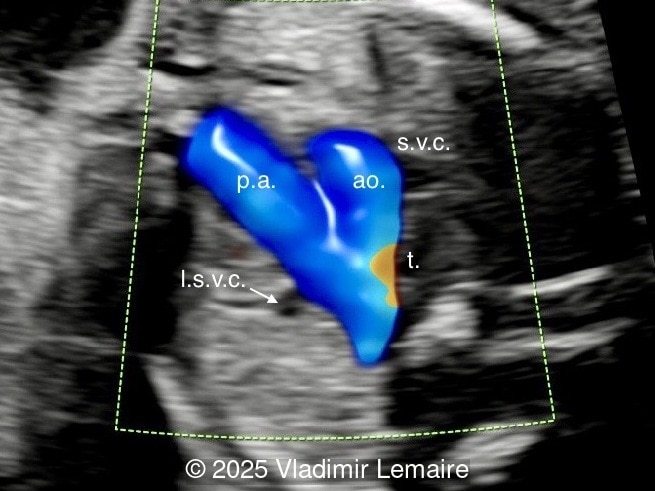

Three-vessel-trachea view with color Doppler.

Image 5 Three-vessel-trachea view with color Doppler.

We present a case of isolated tricuspid atresia type 1 with persistent left superior vena cava. No other extracardiac anomalies were found. Our diagnosis was confirmed after birth.

In the images below, the abbreviations are as follows: RA: right atrium; RV: right ventricle; LV: left ventricle; MV: mitral valve; LA: left atrium; FO: foramen ovale; SVC: superior vena cava; LSVC: left superior vena cava; PV: pulmonary veins; PA: pulmonary artery; MPA: main pulmonary artery; RPA: right pulmonary artery; AO: aorta; dAO: descending aorta; aAO: ascending aorta; DA: ductus arteriosus; T: trachea; * marks the ventricular septal defect.

Image 6 Three-vessel-trachea view with color Doppler.

Color Doppler confirms the diagnosis on grayscale ultrasound, as it demonstrates the lack of blood flow across the tricuspid valve and a patent mitral valve. Due to increased blood flow across the mitral valve, aliasing is typically noted on color Doppler. Mitral valve regurgitation has been associated with a poor outcome. The right ventricular cavity is filled in late diastole from the left ventricle, through the ventricular septal defect. Left-to-right shunting across the ventricular septal defect can be seen on color Doppler. Color Doppler is helpful in the evaluation of flow across the great arteries. Flow across the pulmonary artery is generally antegrade. Pulmonary stenosis should be suspected when the vessel is diminutive in size rather than the demonstration of turbulent flow on color Doppler, which is typically absent in these cases.